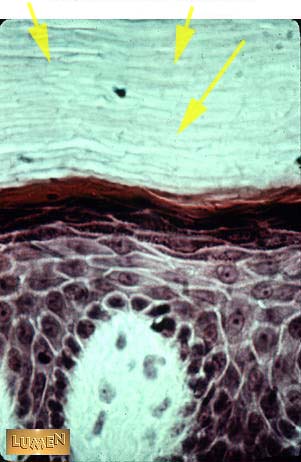

What kind of epithelium is this?

Cornified stratified squamous